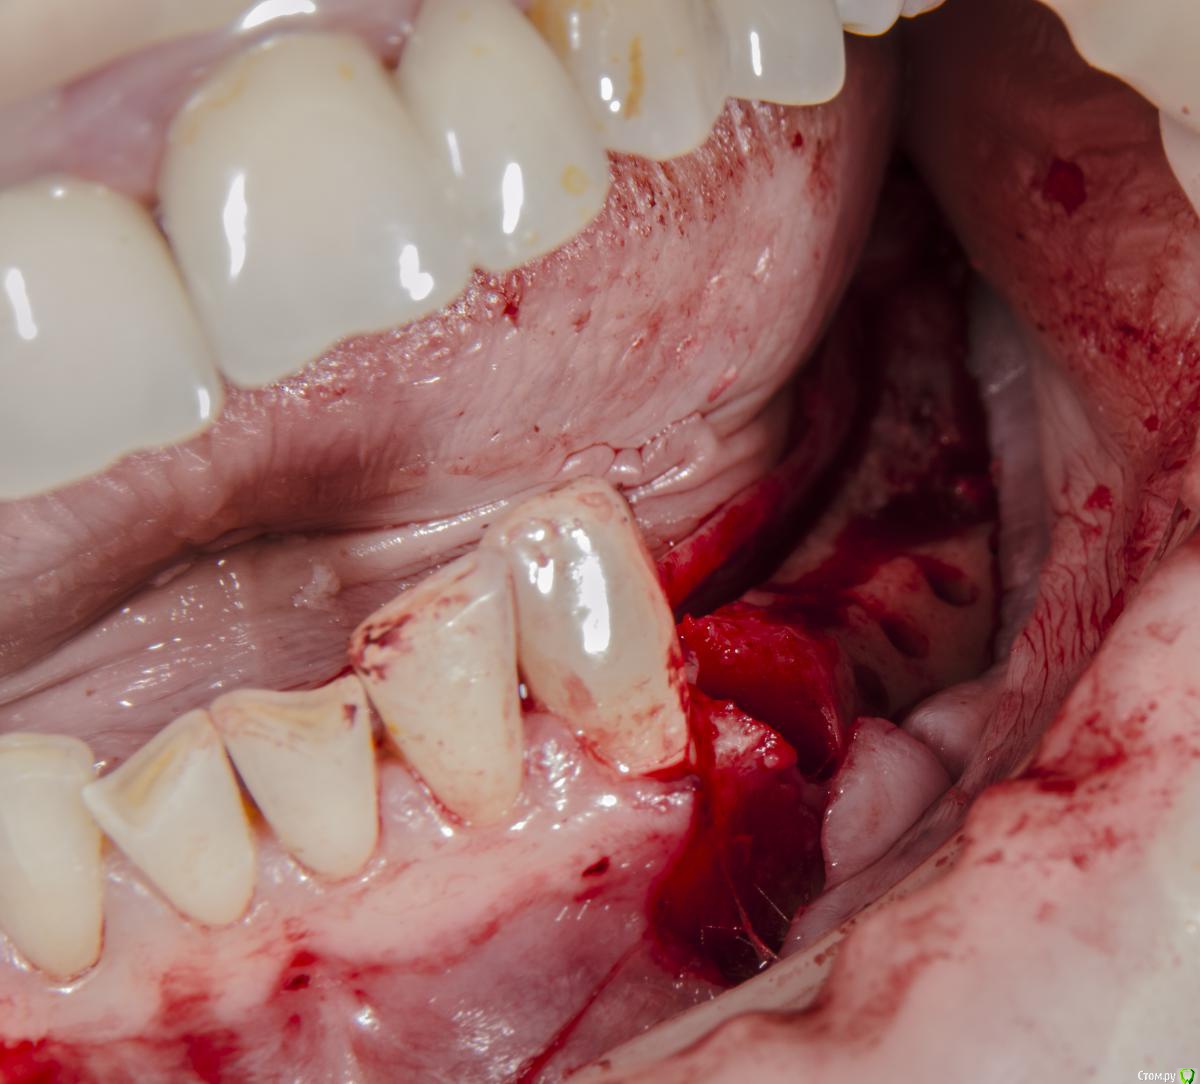

kamranchick Опубликовано 3 мая, 2016 Автор Поделиться Опубликовано 3 мая, 2016 Тут 2ух этапно я пошёл, сначала НКР Ссылка на комментарий

kamranchick Опубликовано 27 мая, 2016 Автор Поделиться Опубликовано 27 мая, 2016 Сори за качество фото... 1 Ссылка на комментарий

kamranchick Опубликовано 1 февраля, 2017 Автор Поделиться Опубликовано 1 февраля, 2017 Аугментата пожалели мне кажется, объёма не особо добавится. Почему винты сразу не захотели? Вроде кости много.Побоялся что если что то пойдет не так то придется все выгребать))Кости если честно не пожалел, не знаю куда он ушел, была ауто кость 2 грамма gen os и 0 5 альфа био графта Ссылка на комментарий